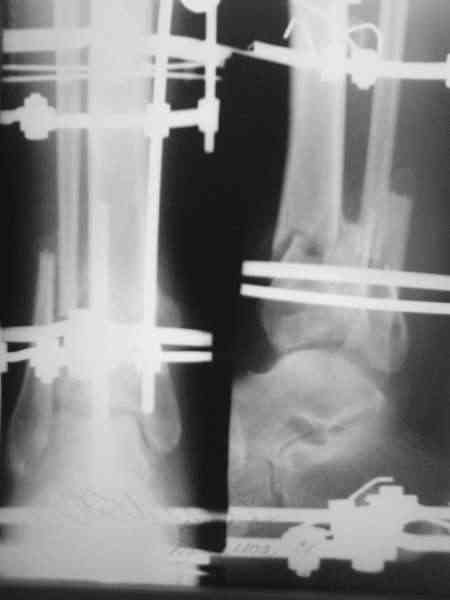

Здравствуйте, коллеги.Сегодня закрыл грануляции расщепленным кожным лоскутом. Начало см здесь Дефект устранил "гофрированием" мягких тканей голени. После этого спицы из дистального отломка удалил. В зоне сближенных отломков идет оссификация. Укорочение голени около 5 см. Что можно предпринять дальше? Тибиализация? Последующее выращивание регенерата в АВФ (в какие сроки оптимально)? Как освободить стопу (и нужно ли сейчас) для разработки в голеностопном суставе? С уважением, Заднепровский Никита Николаевич

Поздравляю с успешным закрытием дефекта голени - гофрирование сработало. Перед свободной кожной пластикой дефекта повторите посев из раны, при обнаружении стрептококков пересадку лучше отложить до полной санации иначе лоскут расплавится. Следующим этапом я бы подумал о перемонтаже аппарата для

создания компрессии в зоне перелома б.б. и проксимальную компактотомию с транспортом костного блока и воостановления длины голени.

Тибиализация это что? Наверное нужно сделать остеотомию(лучше всего косо- поперечную проксильного метафиза пилой Джигли,если получится поднадкостнично). Придется немного перемонтировать аппарат.В ближайщее время,пока не срослась малоберцовая кость, и тянуть не торопясь по 1 мм всутки в 4 подкрутки по 1/4 оборота.Освобождать стопу?!-зачем? Вы убрали спицы из дистального отломка потому что текли. Может имеет смысл провести заново.

АЕ> Тибиализация это что?

Тибиализация малоберцовой кости используется при замещении дефектов большеберцовой кости по методу Илизарова. Спицами с напайками тянут фрагмент малоберцовки к большеберцовке до образования костного блока. В данном случае я расчитываю "укрепить" место перелома фрагментом os fibula который зашел по длине при "гофрировании", так как между отломками рубцовая ткань и расчитывать на истинное сращение здесь, видимо, не придется. Или все же попытаться сдавить отломки tibia с целью раздавливания межотломковых интерпонирующих тканей да начинать "выращивать" остеорегенерат?

Нет, спицы не текли, а появился отек стопы и боли в области сухожилий разгибателей пальцев в конце процесса "гофрирования". Так как репозиции отломков метафиза мне достичь не удалось, то решил убрать их за ненадобностью. Может, попытаться открыто провести репозицию заднего края lag screw задним доступом? Правда время с момента травмы уже 30 дней. Или лучшее враг хорошего? Чем больше занимаюсь этим больным, тем больше вопросов.